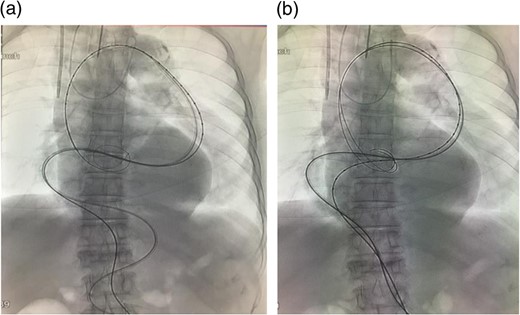

The stent graft (Relay Plus® 38 × 34 × 200 mm, Bolton medical, Barcelona) was introduced through the right common femoral artery. When it reached the distal site of the thoracoabdominal aorta where the angulation was the most severe, the outer hard sheath was left there while the inner flexible sheath was advanced. The flexible sheath was successfully introduced to the proximal site of the thoracoabdominal aorta beyond the angulation (Fig. 3). The stent graft was placed and we confirmed that no endoleak existed (Fig. 4).

Intraoperative arteriogram. (a) The hard sheath was left at the distal site of the angulated part and the flexible sheath was advanced. The angulation was sufficiently reduced by additionally introducing delivery devices for the stent graft (sheath and guide wire). Thus, the stent graft was introduced to the proximal side of the angulated part beyond the aneurysm. Compared to the preoperative contrast CT coronal section image (b) a reduction in the angulation of the proximal aneurysm was observed.